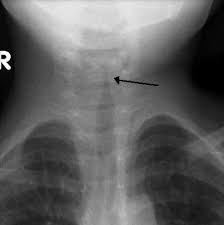

Croup is a viral chest infection that affects young children. It causes a characteristic ‘barking’ cough, a hoarse voice and difficulty breathing. Croup is common and usually mild, but some children will need hospital treatment and breathing support.